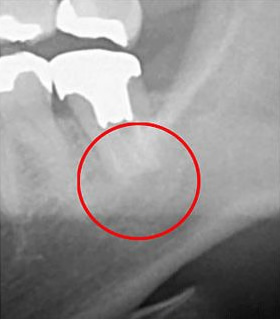

次の画像をご覧ください。これは、CTとレントゲンで同じ患部を撮影した画像です。

左の画像がCT、右がレントゲンで撮影したものです。

左の写真の赤丸で囲んだところは黒い影が映っています。これは「炎症」を示しています。一方、右の写真には黒い影はありません。つまり、レントゲンだけを使って診断すると、この炎症には気付かないということです。放置している間にこの炎症は悪化し、抜歯となってしまうかもしれません。

CTの鮮明な影像によって、正確な診断が可能になります。